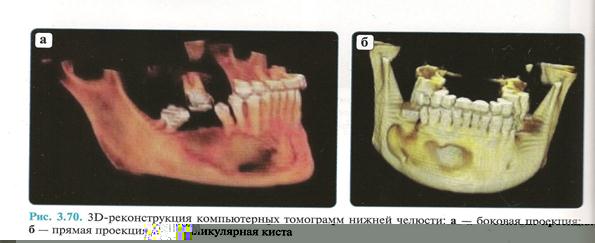

При рентгенологическом исследовании нижней челюсти применяются:

1) Внутриротовая контактная рентгенограмма.

2) Ортопантомограмма.

3) Рентгенограмма нижней челюсти в боковой проекции.

4) Компьпьютерная томограмма.